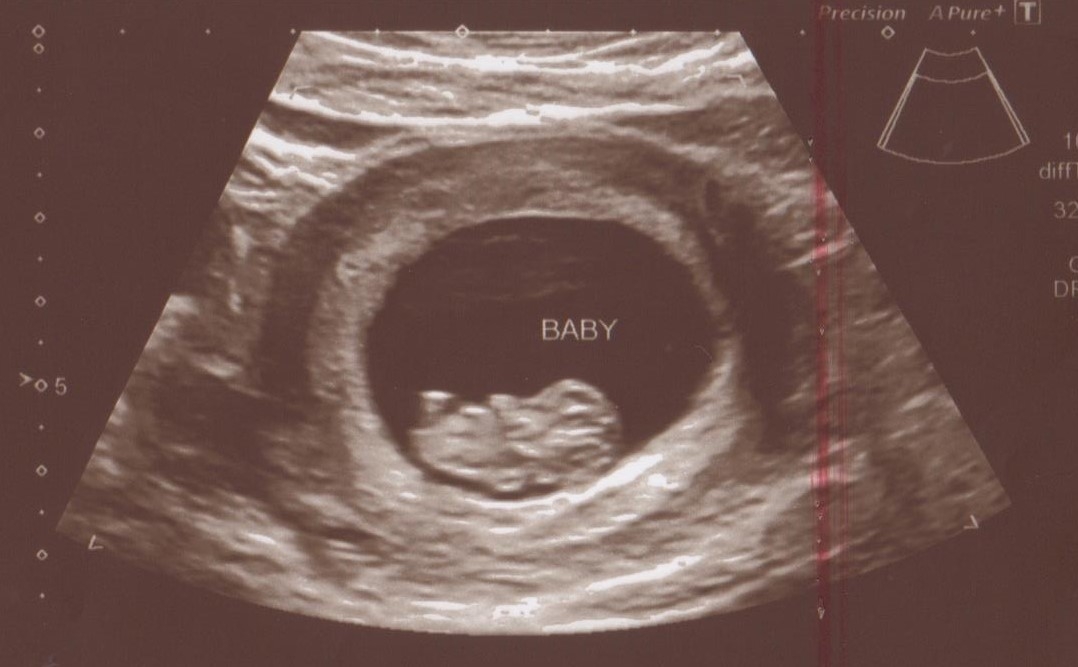

I had my second ultrasound to check for growth. I was either earlier than I had originally thought or something was wrong and I was worried. But everything is perfect!!!!! Baby grew just like it should and we heard a HEARTBEAT!

Here's our little one, measuring one day behind our due date based on LMP, but Dr. didn't see the need to adjust it and confirmed I'm 6 wks 4 days. We didn't get to hear the heartbeat, but we got to see it flutter and beat on the screen, which was so magical to me! I can't believe this is real life.